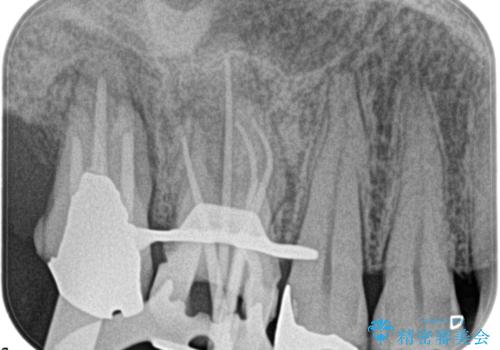

湾曲根管。精密根管治療

- 主治医から補綴前に根管治療を紹介いただいた患者様です。

検査の結果、右上第一大臼歯の診断を、歯髄壊死とし抜髄を行っております。

湾曲根管に対してエラーなく処置を行えております。